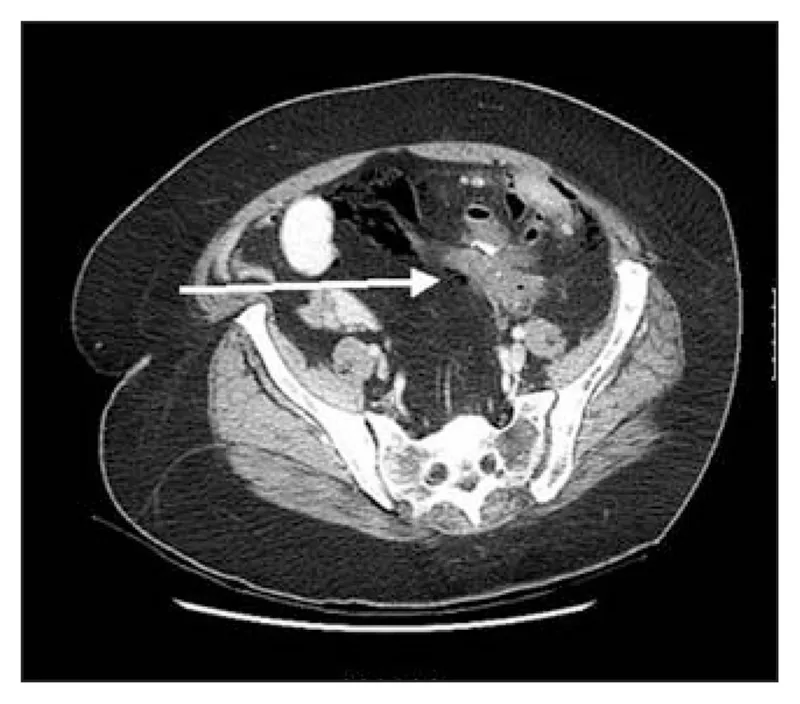

- CT Scan (Abdomen/Pelvis) with Contrast:

- IV contrast: Identifies abscesses, inflammation, and perfusion defects.

- Oral or Rectal contrast: (Water-soluble, e.g., Gastrografin) Directly visualizes contrast extravasation from the lumen.

- CT scan with oral or rectal contrast is the diagnostic gold standard, showing fluid collections or contrast extravasation.